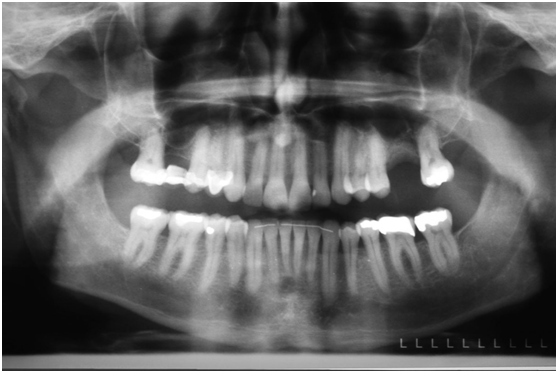

患者的原始片 91/06/13

患者陳先生於91/06/03初診,為一個牙周病患者,合併有右下缺牙。經過保守性牙周處理後,於91/08/14放置右下三顆植體。

完成後大約半年至一年進行一次例行性追蹤檢查,並無特別問題。以下為96/08/13時的追蹤小片,可以見到當時三顆植體的骨高度並無顯著變化。但右下第一小臼齒此時發現有搖動度增加的情形,當時對該顆牙做了咬合調整,降低咬合功能負荷,希望能有所改善。